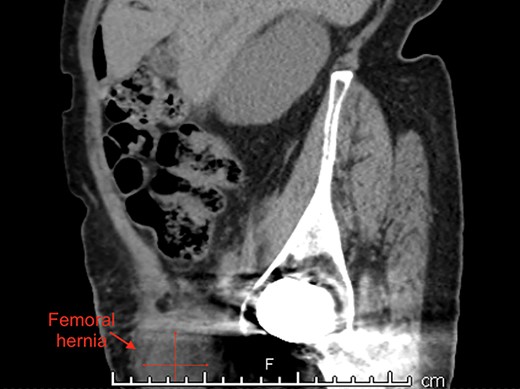

An 87-year-old Caucasian female presented to the emergency department with a 5-day history of worsening right groin pain, with an associated 2-day history of generalized malaise and fatigue. She denied fever, nausea and vomiting or signs of bowel obstruction. Her past medical history included previous right total hip replacement, type 2 diabetes mellitus and chronic renal impairment. Her vitals were normal, and examination revealed a tender right groin lump below the level of the pubic tubercle approximately 4 × 4 cm in size, with overlying erythematous skin changes. Biochemical investigation revealed a normal white cell count of 10.0 × 109/L and neutrophil profile of 7.8 × 109/L but an elevated C-reactive protein (CRP) of 190 mg/L. Contrast-enhanced computed tomography (CT) scan revealed a hypodense rounded lesion measuring 3.8 × 4.3 × 3.1 cm, medial to the right femoral vessels and extending lateral to and below the level of the pubic tubercle in the proximal anterior thigh, most consistent with a incarcerated femoral hernia (Figs. 1–3). The presence of right total hip replacement artifacts precluded accurate assessment for communication of the lesion with the peritoneal cavity.

Imaging modalities also vary in their ability to detect de Garengeot hernias, with MRI being the most sensitive but usually reserved for young pregnant women [9]. Ultrasonography is useful in non-obese patients but is operator-dependent. Hence, CT scan remains the modality of choice as it can at the very least detect a herniating mass projecting below the caecum into the femoral canal with fat stranding [10]. In our case, we relied on CT evidence of possible incarcerated femoral hernia along with a raised CRP of 190 mg/L to influence our decision for surgical intervention.